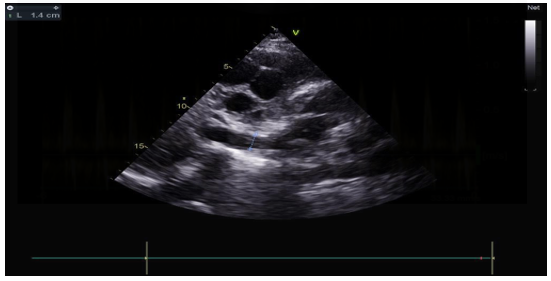

The transthoracic echocardiographic examination revealed (Figures 8 – 18):

- A lobulatedcystic image exerting severe compression on both the right and left cardiac chambers, resulting in hemodynamic disturbance and considerable fluctuation in respiratory flows (Figures 12 – 13,17).

- Elevated left ventricular filling pressure were noted.

We maintained the diagnosis of cardiacpre-tamponade secondary to a large pulmonary hydatid which leaded to an a diastolism alongside pulmonary embolism.